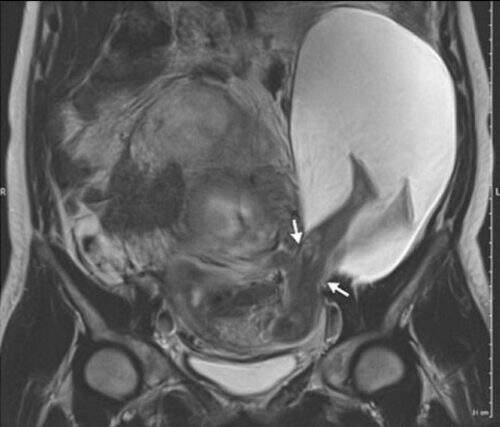

Uma imagem do ultrassom, feita por Pierre-Emanuel Bouet, ginecologista do Hospital da Universidade de Angers (França), mostrou a ocorrência inusitada.

Imagem do ultrassom mostrou a cena rara. (Foto: Reprodução)

A explicação: a gestante de 33 anos apresentou, na 22ª de gravidez, um corte de 2,5 centímetros no útero. Parte do saco amniótico passou pelo rasgo e formou uma “hérnia”, de acordo com o relato do caso feito na revista “The New England Journal of Medicine”.